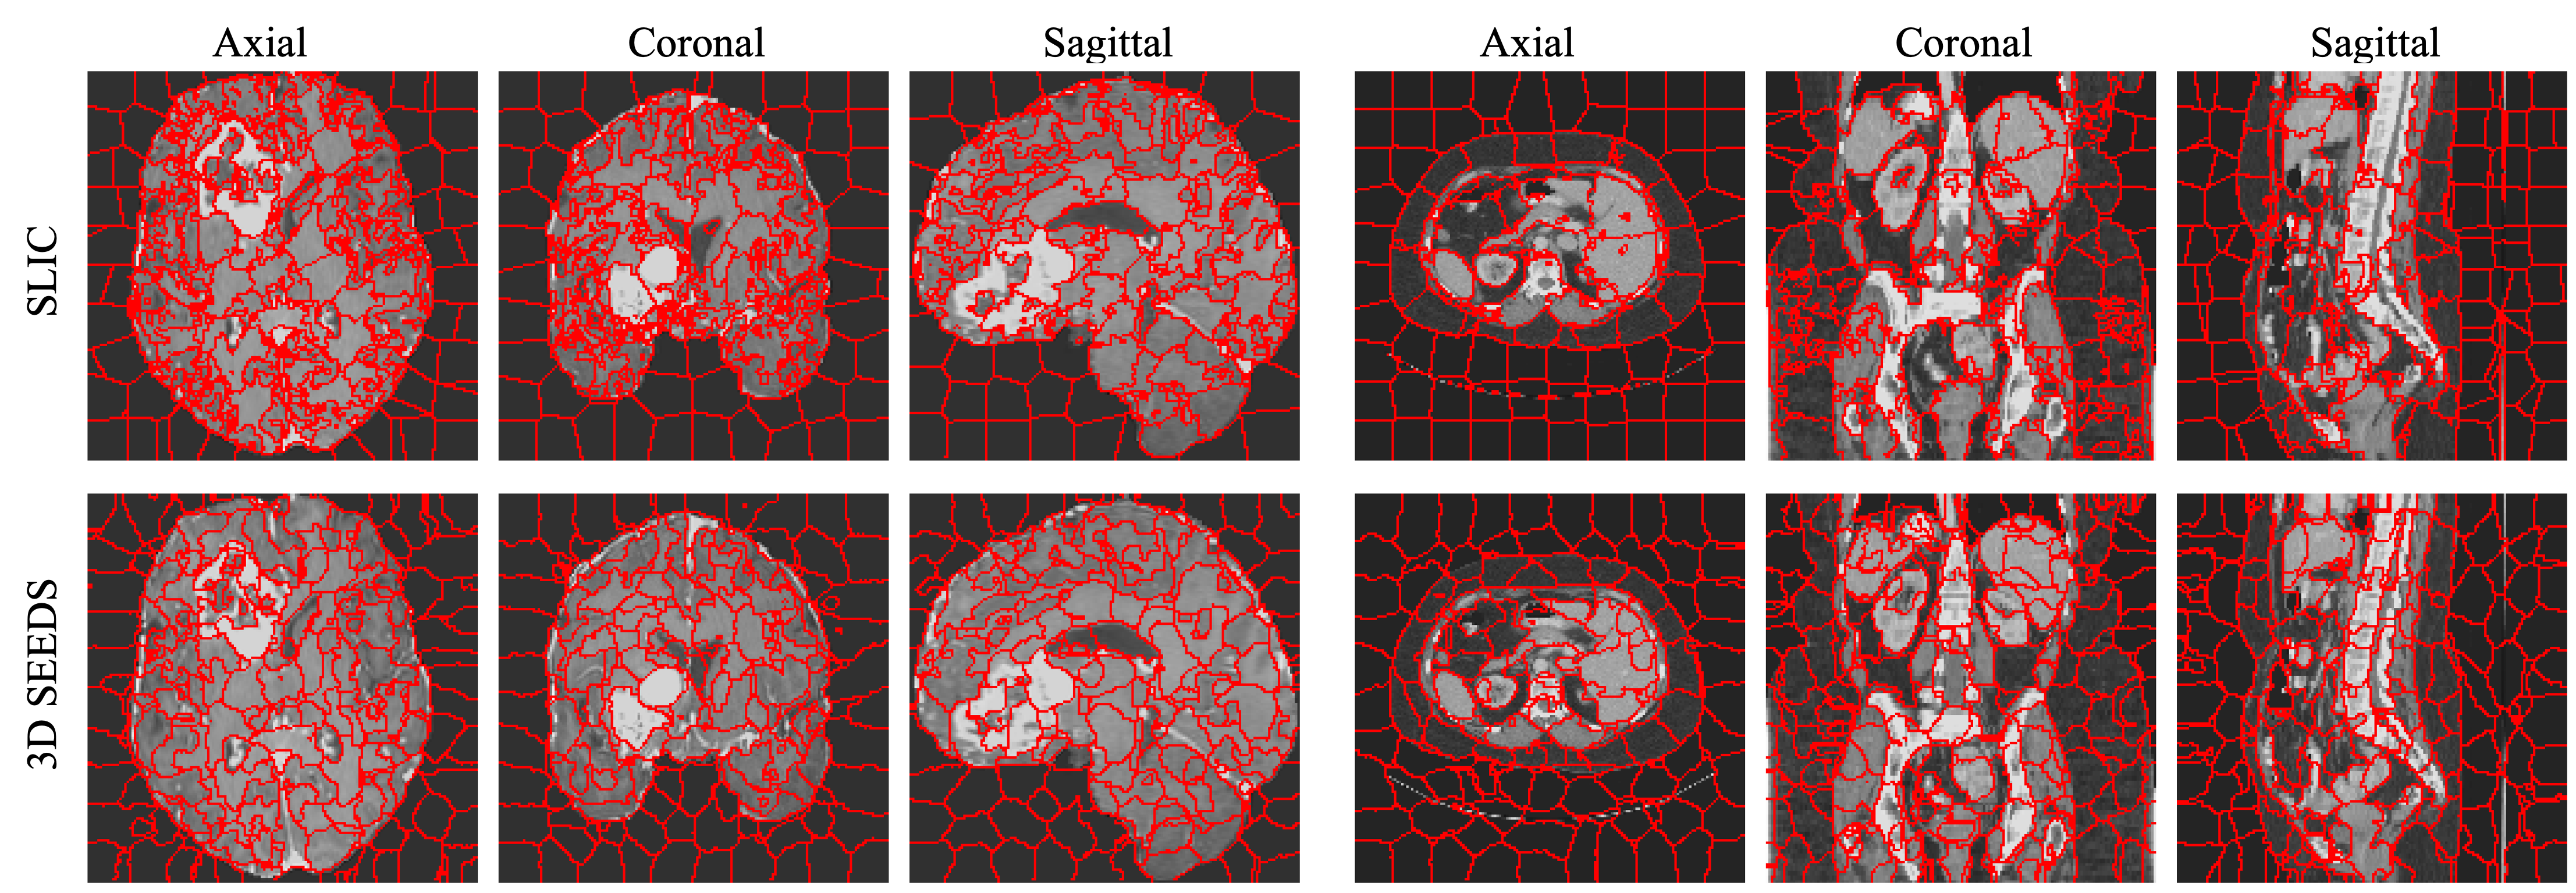

Figure 6: Qualitative result with 1000 supervoxels. Two examples each from the BraTS23-Glioma (left) and BTCV (right) datasets. The orientation for each example is set as [’R’, ’P’, ’I’], with visualizations including axial, coronal, and sagittal views.

Refer to caption

Figure 7: Qualitative result with 4096 sueprvoxels.Two examples each from the BraTS23-Glioma (left) and BTCV (right) datasets. The orientation for each example is set as [’R’, ’P’, ’I’], with visualizations including axial, coronal, and sagittal views.

4.3 Qualitative Results

Figures 6 and 7 present the supervoxel results on the BraTS23-Glioma [3] and BTCV22footnotemark: 2 datasets. To illustrate the results in 3D space, we include axial, coronal, and sagittal views. Compared to SLIC [1], 3D SEEDS generates higher-quality supervoxels, especially when the number of supervoxels is relatively small (i.e., 1000) or on the BTCV dataset. During the experiment, we observe that the number of block-level updates affects the qualitative performance when the number of supervoxels is set to 1000. This suggests that carefully tuning this parameter could further enhance the quantitative performance.